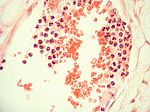

Aktinomykose, HE